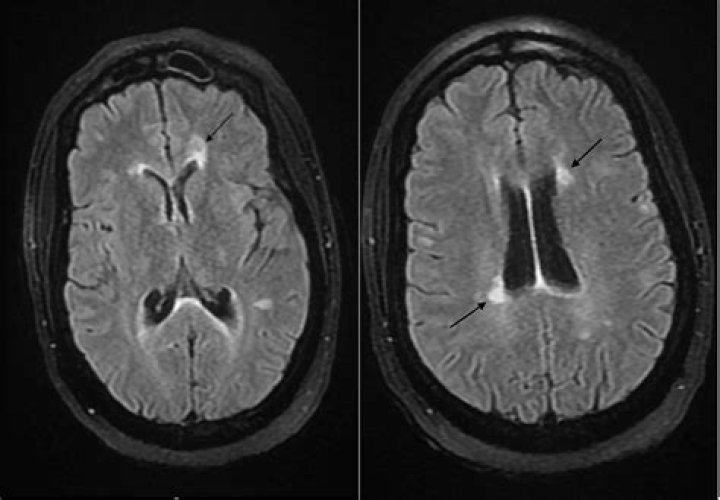

What is a demyelinating lesion?

A demyelinating disease is any condition that results in damage to the protective covering (myelin sheath) that surrounds nerve fibers in your brain, optic nerves and spinal cord. When the myelin sheath is damaged, nerve impulses slow or even stop, causing neurological problems.

In MS, demyelination occurs in the white matter of the brain and in the spinal cord. Lesions or “plaques” then form where myelin is under attack by the immune system. Many of these plaques (or scar tissue) occur throughout the brain over the course of years.